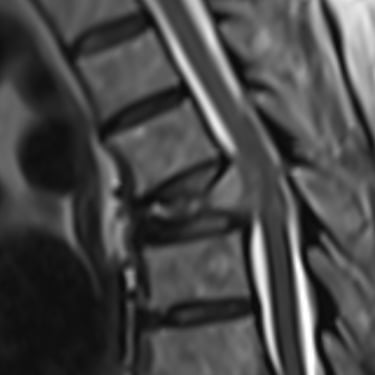

🧠 Hernia Lumbar Sintomática: Estabilidad y Descompresión con Artrodesis y TLIF.

La hernia lumbar sintomática causa dolor lumbar y radicular persistente. La artrodesis con tornillos transpediculares y TLIF es una opción quirúrgica eficaz para descomprimir las raíces nerviosas, estabilizar la columna y mejorar la calidad de vida del paciente.